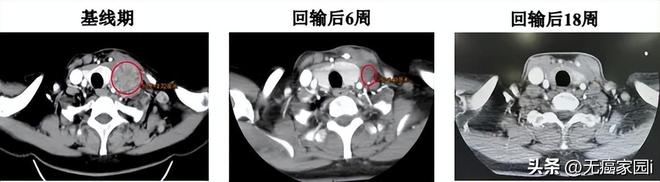

TIL治疗过程,受试者除预处理过程短暂血液学毒性外无其他不良反应。回输第6周肿瘤缩小45%,肿瘤标志物恢复正常,癌痛减轻、颈部淋巴结消失;第12周靶病灶完全缓解(CR),18周时CR仍维持。

患者接受TIL治疗前和治疗后6周、18周增强CT扫描结果(左侧颈部淋巴结) (图源上海九院官网,侵删)